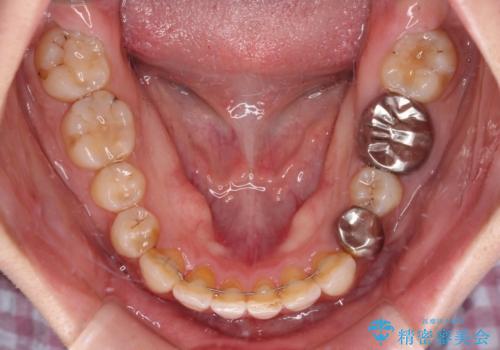

- 前歯のデコボコと深い咬み込みを気にして来院された患者様です。

インビザラインを用いて、前歯の叢生を解消するとともに、深い咬み合わせ(ディープバイト)を改善していくこととしました。

奥歯を後方に直立させることで深い咬み合わせを改善を図り、隠れていた下顎前歯が見えるほどになりました。